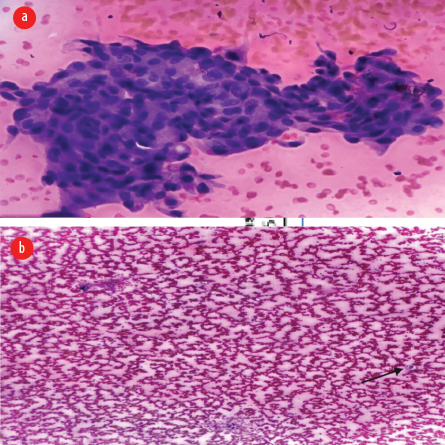

Fine-needle aspiration cytology showed a predominantly hemorrhagic and proteinaceous background, with a few mucinous flakes and tiny clusters of benign epithelial cells. Cyst macrophages were also present, suggesting a benign cystic lesion [Figure 2a and b]. Upon excision, the cyst measured 4 × 3 × 2 cm, and released 5 mL of hemorrhagic fluid. Gross examination revealed a grey-white cyst wall with papillary excrescences [Figure 3]. Histopathological examination showed columnar epithelial cells lining the cyst, along with dilated thyroid follicles containing colloid eosinophilic material [Figure 4a]. Papillary projections lined by malignant cells with eosinophilic cytoplasm, overlapping nuclei, nuclear grooves, and pale chromatin were identified [Figure 4b and c].

Figure 2: (a) Fine-needle aspiration cytology showing tiny clusters of benign epithelial cells and (b) tiny clusters along with cyst macrophage (black arrow).